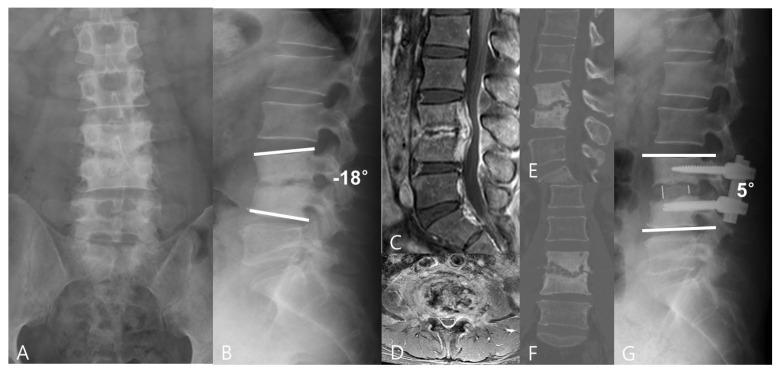

(1) Background: This study evaluated the efficacy and safety of a minimally invasive oblique lumbar interbody fusion (OLIF) using polyetheretherketone (PEEK) cages for the treatment of lumbar pyogenic spondylodiscitis. (2) Methods: Fifty-one patients with single-level lumbar pyogenic spondylodiscitis were included in the study. Patients were divided into two groups: anterior lumbar interbody fusion with a tri-cortical iliac bone graft (ALIF+ tri-cortical iliac bone graft) (n = 28) and OLIF using PEEK cages with an autologous bone graft (OLIF+ PEEK cages) (n = 23). Perioperative radiographic parameters, complications, and clinical outcomes in both groups were analyzed and compared. (3) Results: The postoperative and final follow-up LL (lumbar lordosis) and RL (regional lordosis) were improved in both groups ( < 0.001). But, compared with the ALIF group, the OLIF group had more improvement of the RL. The operation time was 79 min for the OLIF group and 101 min for the ALIF group ( < 0.05). The intraoperative blood loss was 92 mL for the OLIF group and 114 mL for the ALIF group ( < 0.05). Significant clinical improvement was observed in visual analogue scale scores for the back and Oswestry Disability Index in both groups ( < 0.001). There was no recurrence of infection. (4) Conclusions: Compared with the ALIF group, the OLIF group had more improvement in radiographic and clinical outcomes. Thus, OLIF using PEEK cages with an autologous bone graft could be proposed for the surgical treatment of lumbar pyogenic spondylodiscitis.

(1)背景:本研究评估了使用聚醚醚酮(PEEK)椎间融合器的微创斜外侧腰椎椎间融合术(OLIF)治疗腰椎化脓性脊柱炎的疗效和安全性。(2)方法:本研究纳入了51例单节段腰椎化脓性脊柱炎患者。患者分为两组:前路腰椎椎间融合术加三面皮质髂骨移植(ALIF + 三面皮质髂骨移植)(n = 28)和使用PEEK椎间融合器加自体骨移植的OLIF(OLIF + PEEK椎间融合器)(n = 23)。分析并比较两组的围手术期影像学参数、并发症和临床结果。(3)结果:两组术后及末次随访时的腰椎前凸(LL)和节段性前凸(RL)均得到改善(<0.001)。但是,与ALIF组相比,OLIF组的RL改善更多。OLIF组的手术时间为79分钟,ALIF组为101分钟(<0.05)。OLIF组术中出血量为92毫升,ALIF组为114毫升(<0.05)。两组的背部视觉模拟评分和Oswestry功能障碍指数均有显著的临床改善(<0.001)。感染无复发。(4)结论:与ALIF组相比,OLIF组在影像学和临床结果方面改善更多。因此,使用PEEK椎间融合器加自体骨移植的OLIF可用于腰椎化脓性脊柱炎的手术治疗。